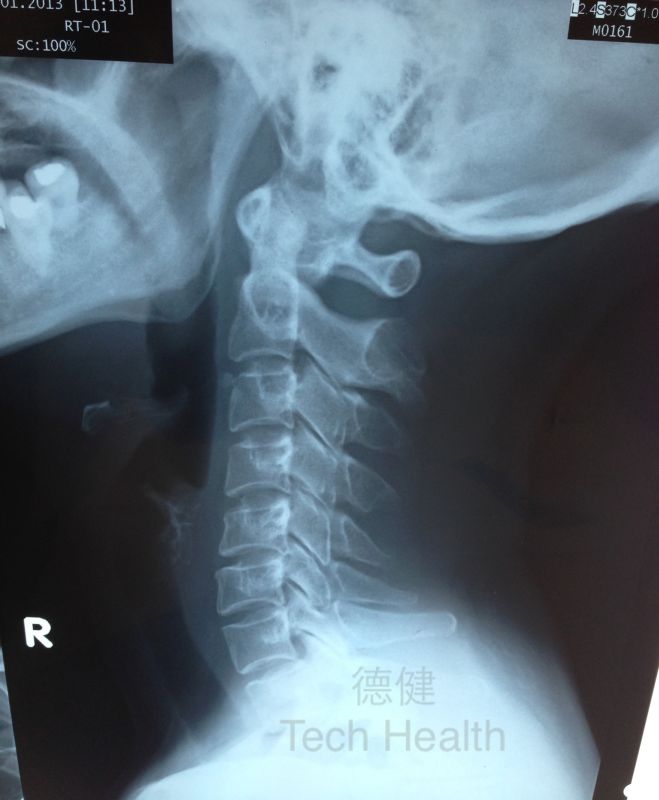

個案六 - 譚女士 45歲 - 從X光片檢查發現患者頸椎生理弧度異常,並患有退行性頸椎病。

2.從X光片檢查發現患者頸椎生理弧度異常,並患有退行性頸椎病。